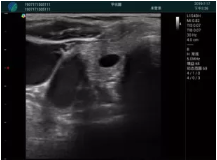

可視化穿刺引導(dǎo)

M20實(shí)時(shí)引導(dǎo):向包塊后方間隙注射利多卡因

清晰顯示腺體內(nèi)低回聲快影,邊界清晰,包膜較光滑

確定進(jìn)針路徑并實(shí)時(shí)監(jiān)測(cè)抽吸針與腫塊位置關(guān)系

抽吸針進(jìn)入腫塊內(nèi)部進(jìn)行旋切

抽吸過程中可見腫塊明顯縮小,并根據(jù)腫塊位置改變針道位置

抽吸旋切后再進(jìn)行超聲復(fù)查,原腫塊區(qū)域未見殘留組織及出血

超聲引導(dǎo)下抽吸旋切取出的腫塊組織